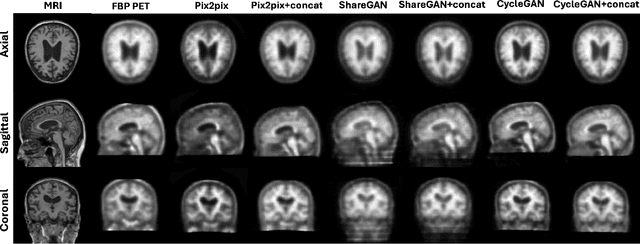

Abstract:Cross-modality translation between MRI and PET imaging is challenging due to the distinct mechanisms underlying these modalities. Blood-based biomarkers (BBBMs) are revolutionizing Alzheimer's disease (AD) detection by identifying patients and quantifying brain amyloid levels. However, the potential of BBBMs to enhance PET image synthesis remains unexplored. In this paper, we performed a thorough study on the effect of incorporating BBBM into deep generative models. By evaluating three widely used cross-modality translation models, we found that BBBMs integration consistently enhances the generative quality across all models. By visual inspection of the generated results, we observed that PET images generated by CycleGAN exhibit the best visual fidelity. Based on these findings, we propose Plasma-CycleGAN, a novel generative model based on CycleGAN, to synthesize PET images from MRI using BBBMs as conditions. This is the first approach to integrate BBBMs in conditional cross-modality translation between MRI and PET.